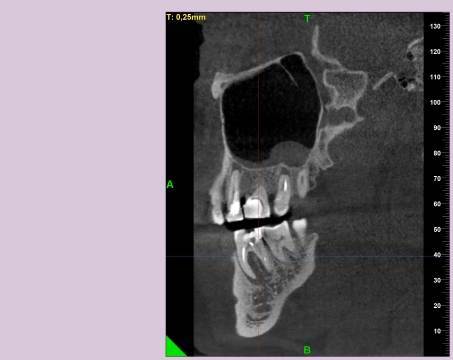

КТ от 04.03.2024

69273_3.jpg.f56a31dc1d8d53085767a9a52915128c.jpg69273_4.jpg.f9ec255bedbdb9fde8159318d3cb1fd9.jpg69273_5.jpg.36a7a942d403dd2eb062e5a4b2b58a52.jpg69273_6.jpg.492d3fbca3808fbdf58c86056b2fe0c3.jpg69273_7.jpg.f9bfdd5d593504dc7bd3710ece18aa4f.jpg69273_8.jpg.853e2342e6f2329a2e89c8939c2aad6f.jpg69273_11.jpg.e495813d50bf007f7165bf5f5dfec4b3.jpg69273_12.jpg.49b3cf66b4dd26b5cd68a91b2684e402.jpg69273_13.jpg.5d61b621b8e8b2c473ad6a8aca42502d.jpg

Добрый день! В данный момент прохожу лечение 46 зуба. Улучшений нет, поэтому возникли сомнения в тактике лечения выбранной моим стоматологом.

Лекарство было извлечено, и каналы запломбированы гуттаперчей. Доктор предупредила, что зуб будет болеть, и прийти я должен после того, как зуб "успокоится", болевые ощущения пропадут. На третий день десна под зубом вспухла, и начала сочиться сукровица. Я решил сделать новое КТ(28.05.2024), и с результатом сходить в другие клиники для консультации. В первой мне сказали, что доктор не должна была начинать лечение, потому, что зуб идет под удаление. Во второй клинике, что попытаться вылечить можно, но изначально были допущены ошибки в лечении, и надо переделывать.

Что-то можно сделать с 46 зубом для сохранения, или он должен быть удален?